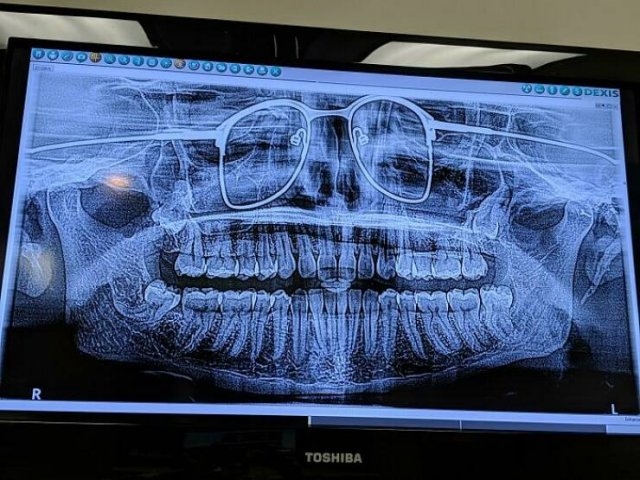

Fails Staff 07/21/2025 Pictures Comments1.5k 1 0Sometimes people make very terrible mistakes. 51525354555657585960616263646566 Pages ◄1 2 Share this post:Click to share on FacebookClick to share on TwitterClick to share on TumblrClick to share on PinterestClick to share on RedditClick to email this to a friend